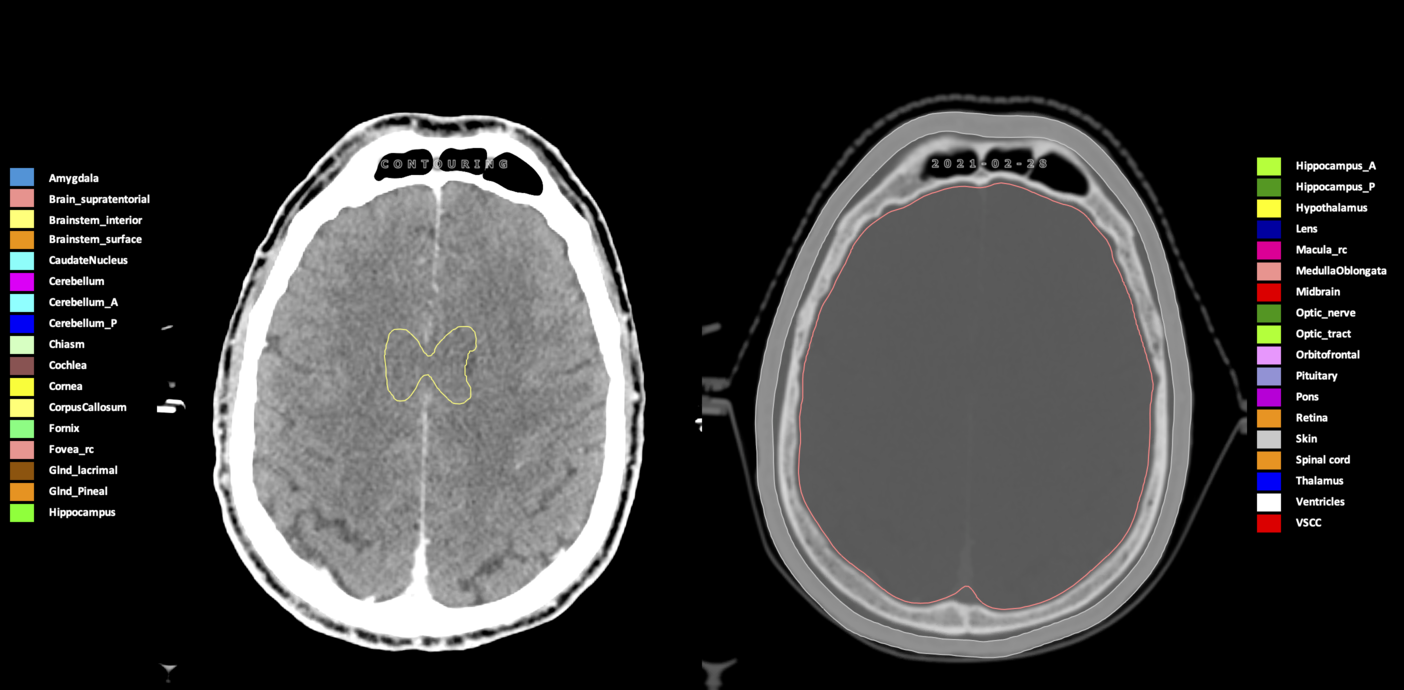

Included are all OARs known to be relevant for radiation-induced toxicity in neuro-oncology: brain, brainstem (midbrain, pons, medulla oblongata), chiasm, cerebellum (anterior & posterior), cochlea, cornea, hippocampus (anterior & posterior), hypothalamus, lens, lacrimal gland, optic nerve, pituitary, skin, and vestibular & semicircular canals. To further facilitate research on cognition, vision and radiological changes after irradiation of the brain, potential clinically-relevant OARs are included: amygdala, caudate nucleus, cerebellum (anterior & posterior), corpus callosum, fornix, macula, optic tract, orbitofrontal cortex, periventricular space (PVS), pineal gland, and thalamus.

Three-dimensional delineation of the 25 consensus OARs for neuro-oncology are shown on CT (WW/WL 120/40, 3000/600), 3T MR images, (T1Gd, T2FLAIR 1mm) and 7T MR (MP2RAGE 0.7 mm). All are presented in transversal, sagittal and coronal view.